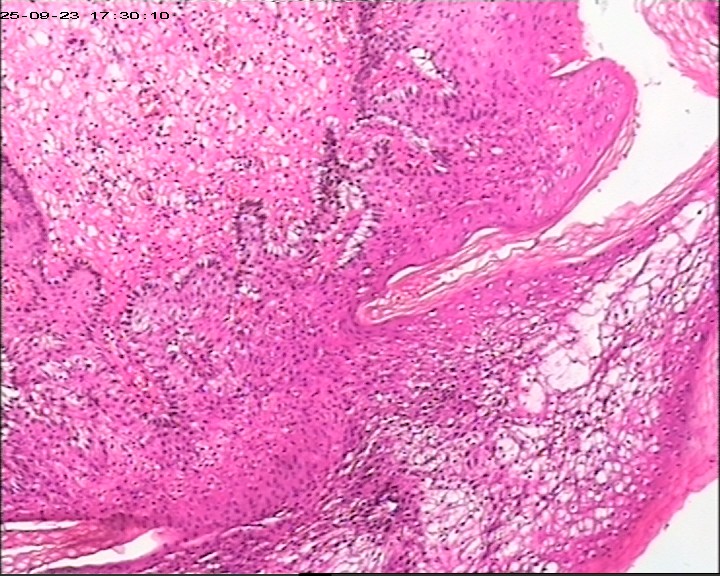

肛周脓肿组织,请帮忙看看,谢谢

肛周出血肿块伴疼痛,红肿6天。脓肿切开引流术+内痔结扎术

臀部皮肤病损

灰白灰红带皮组织3块,大小为3*2*0.5cm

鳞状上皮增生伴湿疣样改变

生炎+出血。

急、慢性炎,伴出血。